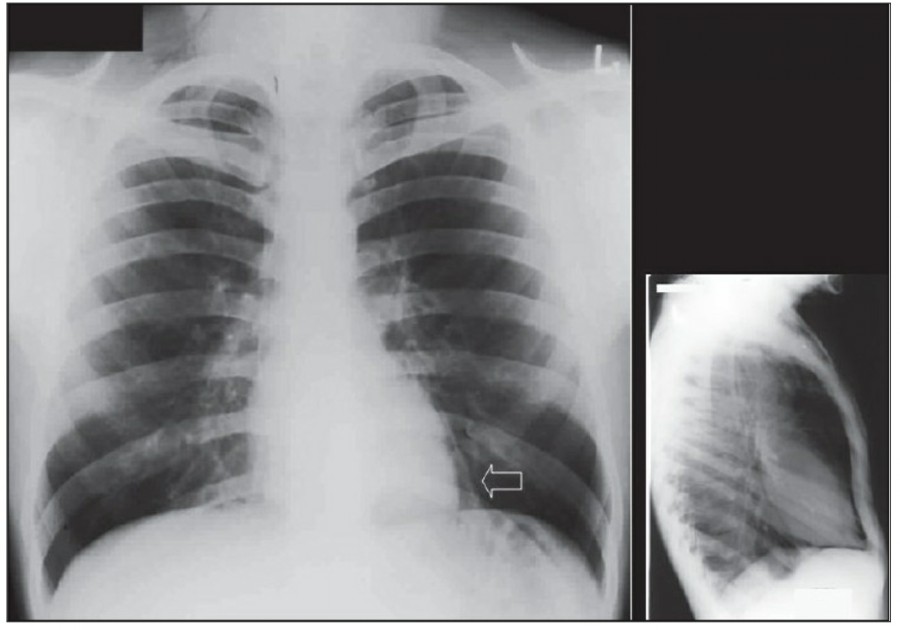

Pneumothorax

공기는 nondependent position으로 위치하므로, X ray상에서는 환자 자세에 따라 다르게 나타난다. Erect position에서 공기는 lung의 apicolateral surface에 위치하고 얇고 하얀 pleural line이 나타나며 그 뒤로 lung marking이 보이지 않는다.

하지만 pleural line 뒤로 lung marking이 존재한다고 해서 pneumothorax를 배제할 수 없다. Pneumothorax의 진단은 특히 parenchymal disease가 있을 때 진단하기 힘든데, 이는 compliance의 변화 때문에 collapse가 잘 안 되기 때문이다. Skin fold가 pneumothorax와 비슷하게 보이기도 한다.

중환자에서 pneumothorax의 진단은 종종 supine radiograph에서 내릴 수 있다. Supine position에서 공기는 anteromedial 방향으로 모이게 되는데, apical air collection이 있을 경우 large pneumothorax가 있음을 시사한다. 공기는 lung과 diaphragm 사이의 subpulmonic location에 trap 되어 있을 수도 있다. 공기가 costophrenic sulcus로 anterolateral extension 될 경우, 이 costophrenic sulcus의 radiolucency를 증가시키는데, 이를 deep sulcus sign이라고 한다. Subpulmonic pneumothorax의 다른 특징으로 diaphragm의 superior surface와 IVC 윗부분이 뚜렷하게 보일 수 있다.

중환자에서 tension pneumothorax의 진단은 매우 힘들다. ARDS와 같은 lung의 병리적인 기전이 lung compliance를 감소시킴으로써 total lumg collapse를 막는다. 또한 tension pneumothorax의 특징인 mediastinal shift가 PEEP으로 인해 나타나지 않을 수 있다. Chest X ray 상에서 tension pneumothorax는 hemidiaphragm의 depression이나 heart border, SVC, IVC의 이동으로 나타날 수 있다.